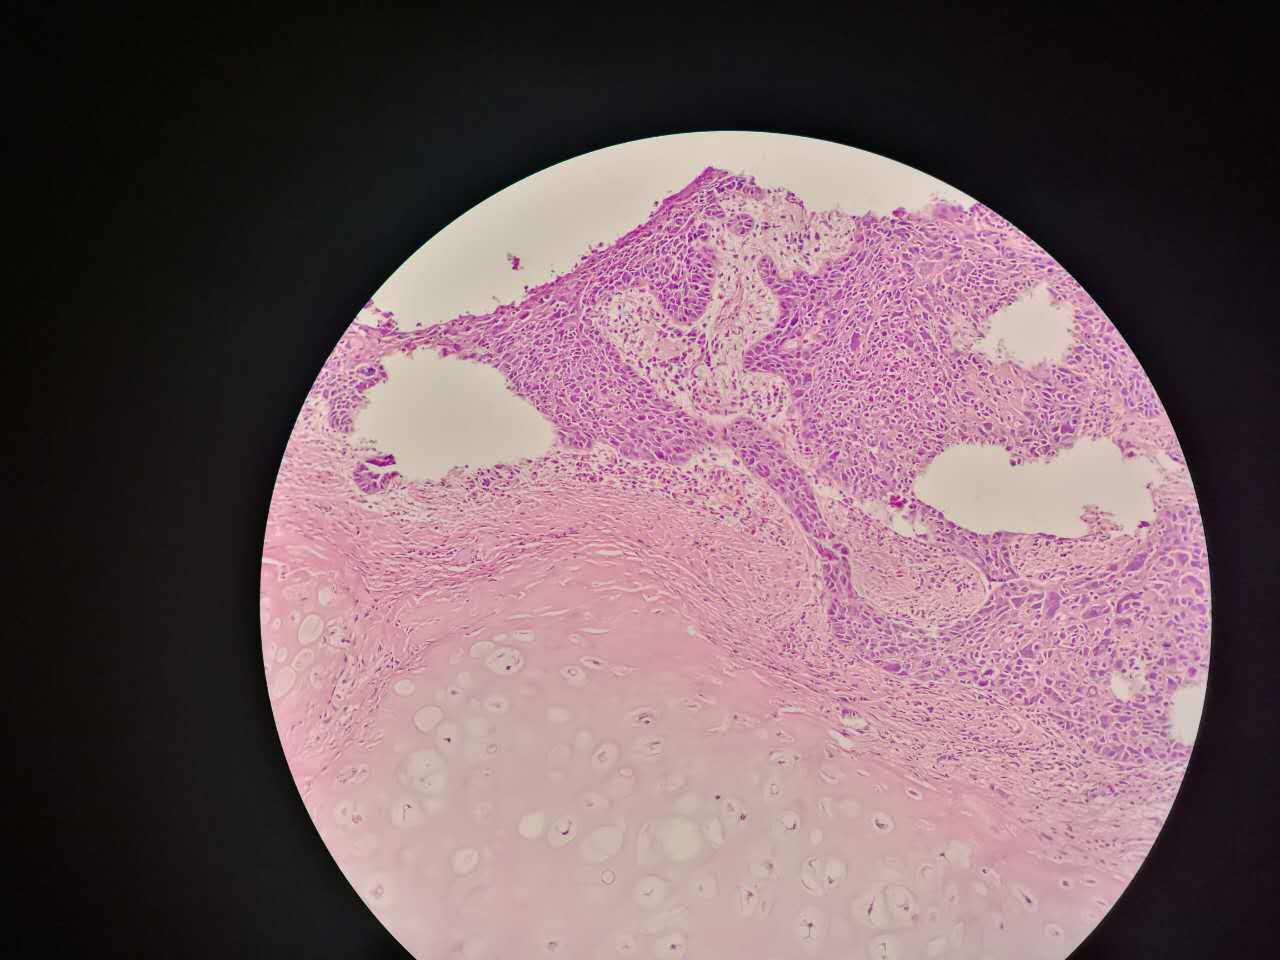

支气管柱状上皮鳞状化生

鳞状化生

支气管粘膜鳞癌

结构紊乱,细胞异型

支气管鳞癌

复层排列,细胞有很多层

基底侧边界清楚

鳞癌是从支气管鳞化,异型增生,癌变,浸润,这么发展过来的。强调!

这个下面的软骨说明了是大气管,中央型

鳞癌组织学本质上没有周围型!

因为都是发生于支气管的,没有发生于肺泡和呼吸性细支气管的。